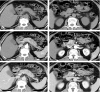

This study aimed to determine whether changes in contrast-enhanced computed tomography (CT) parameters could predict postsurgery overall and progression-free survival (PFS) in pancreatic cancer patients. Seventy-nine patients with a final pathological diagnosis of pancreatic adenocarcinoma were included in this study from June 2008 to August 2012. Dynamic contrast-enhanced (DCE) CT of tumors was obtained before curative-intent surgery. Absolute enhancement change (AEC) and relative enhancement change (REC) were evaluated on DCE-CT. PFS and overall survival (OS) were compared based on CT enhancement patterns. The markers of fibrogenic alpha-smooth muscle antigen (α-SMA) and periostin in tumor specimens were evaluated by immunohistochemical staining. The χ test was performed to determine whether CT enhancement patterns were associated with α-SMA-periostin expression levels (recorded as positive or negative). Lower REC (<0.9) was associated with shorter PFS (HR 0.51, 95% CI: 0.31-0.89) and OS (HR 0.44, 95% CI: 0.25-0.78). The α-SMA and periostin expression level were negatively correlated with REC (both P = 0). Among several CT enhancement parameters, REC was the best predictor of patient postsurgery survival. Low REC was associated with a short progression-free time and poor survival. The pathological studies suggested that REC might be a reflection of cancer fibrogenic potential.